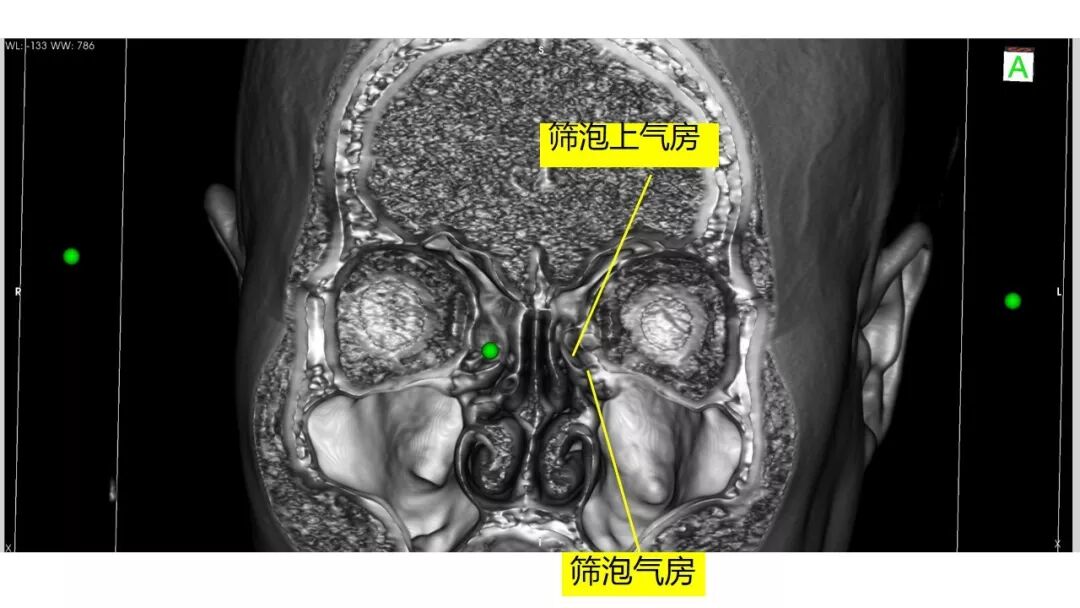

内镜修补